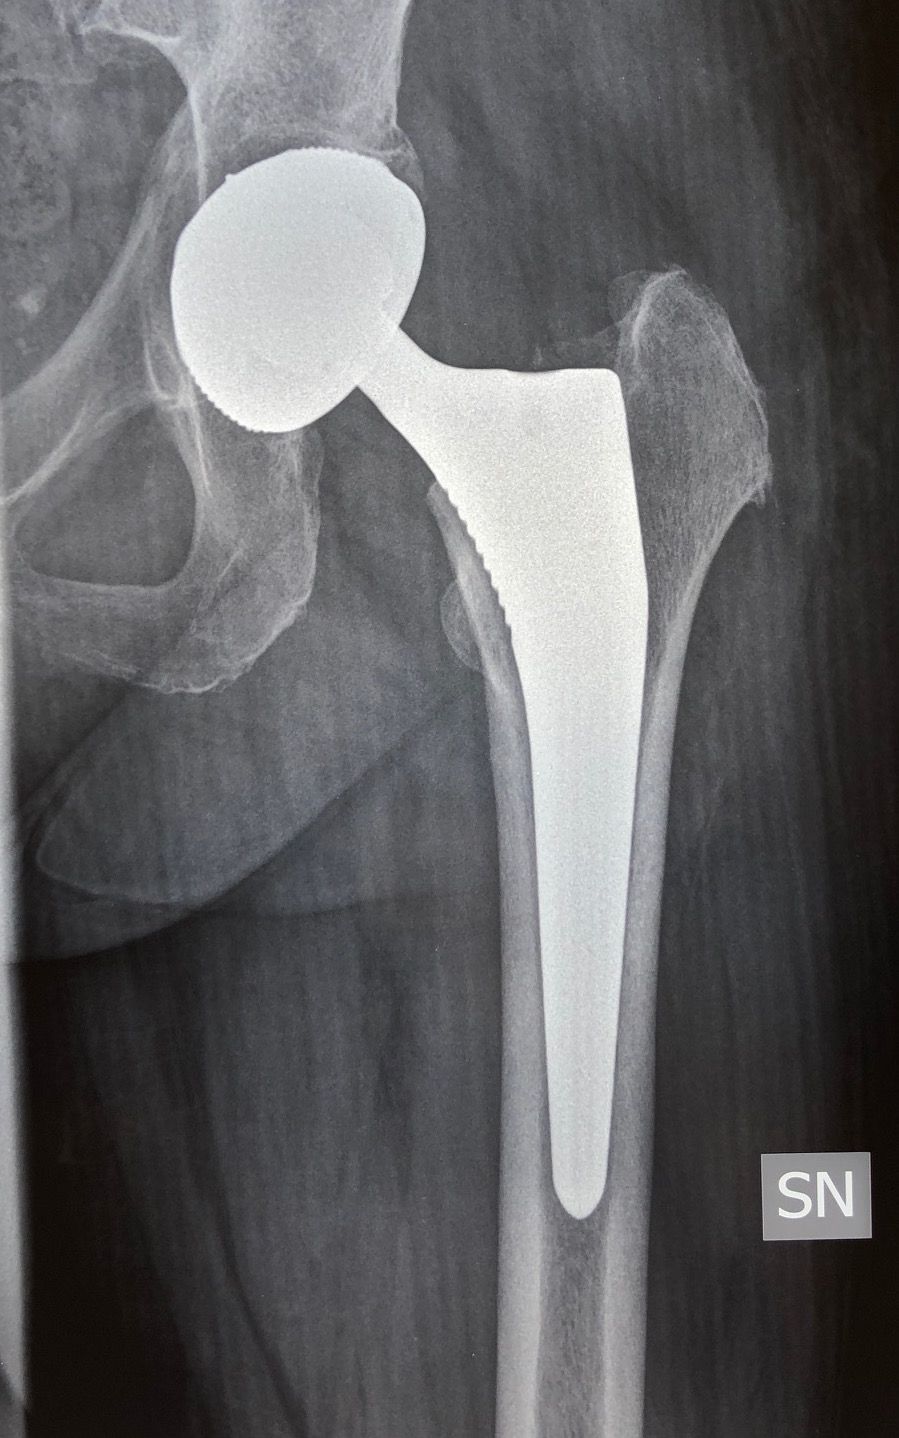

Sono specializzato nell'impianto di protesi di ginocchio ed anca in caso di patologie degenerative artritiche o necrotiche. Utilizzo protesi di ultima generazione, le protesi di ginocchio vengono applicate utilizzando una maschera creata su misura per ogni paziente, quelle di anca sono studiate per ridurre al minimo il rischio di lussazione (principale complicazione di questo tipo di intervento).

Foto e video